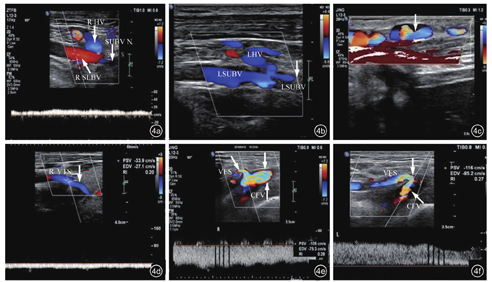

颈内静脉超声检查(2016-12-10):双侧颈内静脉(图3a, 图3b, 图3c)、双侧头臂静脉血栓形成(完全型,图3d, 图3e, 图3f)。双侧锁骨下静脉血栓(图4a, 图4b, 图4c);腹壁浅静脉逆流经大隐静脉至股总静脉下腔静脉回心,胸腹壁迂曲静脉扩张(反流,图4d, 图4e, 图4f)。

注:RHV为右侧头静脉RSUBV为右侧锁骨下静脉;N为近端;LHV为左侧头静脉;LSUBV为左侧锁骨下静脉;RVTS为右侧甲状腺上静脉;VES为腹壁浅静脉;CFV为股总静脉